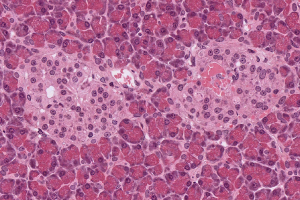

Des lymphocytes T CD4+ sont infectés avec le VIH-1 pendant 48 heures puis cultivés pendant 24 h avec des anticorps neutralisant à large spectre (broadly neutralizing antibodies – bNAbs). A. Observation en microscopie électronique à transmission. Rétention virale au site de bourgeonnement, comprenan...